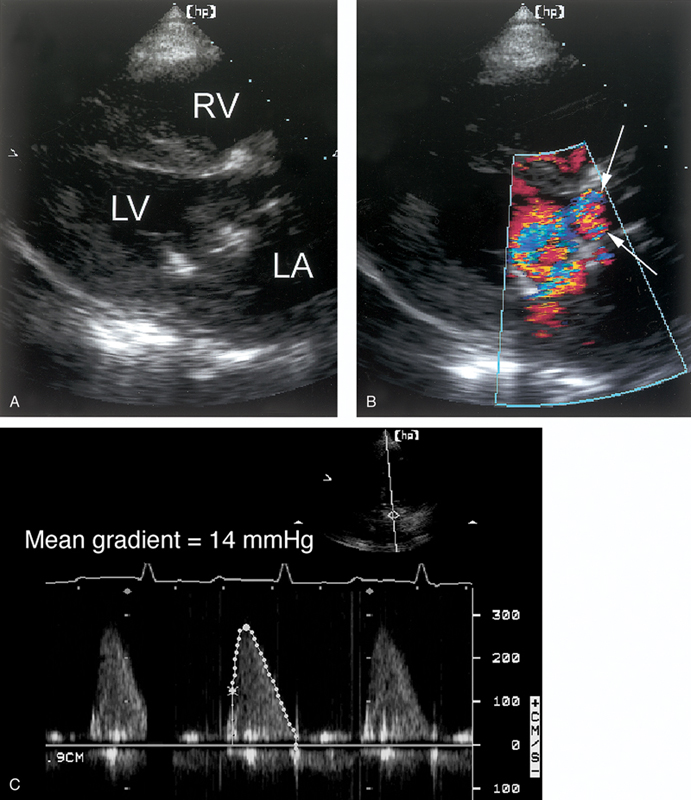

فحوصات تشخيصية لبعض امراض القلب والشرايين التاجية